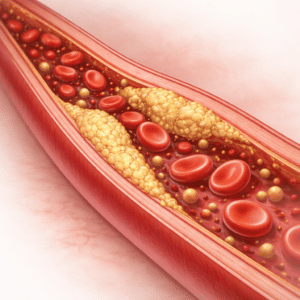

Cholesterol Control Made Simple: Science-backed Ways to Improve Cholesterol Levels

When it comes to protecting your heart and health, cholesterol control plays…

Cholesterol Control: Foods, Habits, and Heart Health

High cholesterol is a major risk factor for heart disease, but it…